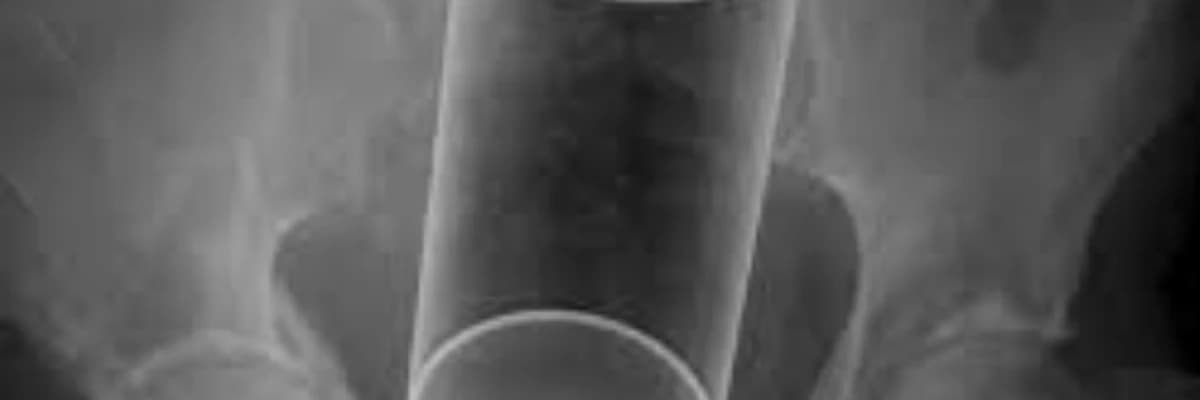

Bağırsaqda yad cisimlərin olması simptomlara səbəb ola bilər. Bu simptomlar yad cismin ölçüsünə və yerindən və bağırsaqlarda necə reaksiya verdiyindən asılı olaraq dəyişə bilər. Yad cisim bağırsaqlarda tıxanıqlığa və ya perforasiyaya səbəb ola bilər. Simptomlara qarın ağrısı, ürəkbulanma, qusma, qəbizlik, qanlı nəcis, qızdırma və hətta şok əlamətləri daxil ola bilər. Düz bağırsaqlarda yad cismin diaqnozu adətən tibbi görüntüləmə testləri (məsələn, rentgen, kompüter tomoqrafiyası) və bəzən endoskopik müayinələrdən (kolonoskopiya) istifadə edilir. Müalicə yad cismin ölçüsünə və yerləşdiyi yerə və bağırsaqlara necə təsir etdiyinə görə dəyişir. Kiçik yad cisimlər bəzən təbii yolla keçə bilər və ya endoskopik yolla çıxarıla bilər. Ancaq böyük olan və ya bağırsaqları zədələyən yad cisimlər cərrahi müdaxilə tələb edə bilər. Bundan əlavə, yad cisimlə əlaqəli ağırlaşmaların müalicəsi də vacibdir.